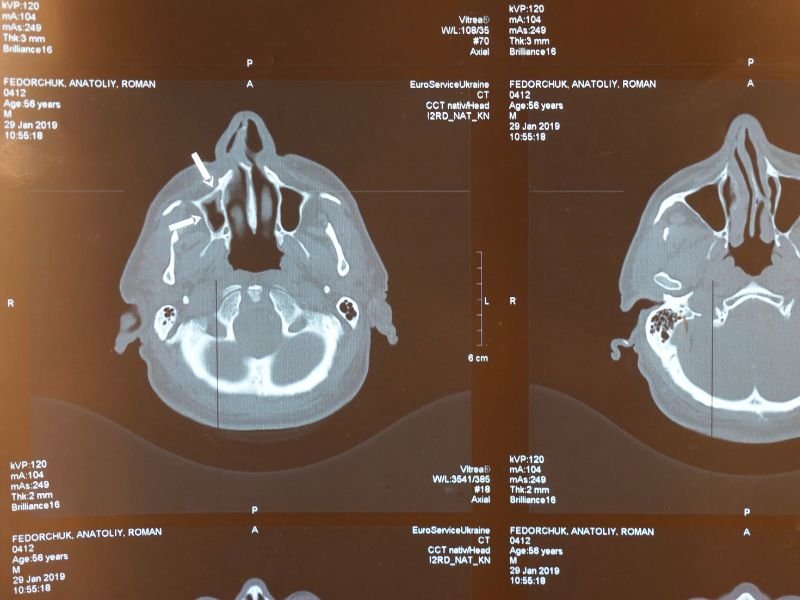

Infiltração para Dor de Cabeça em Criciúma A dor de cabeça é uma condição comum que pode afetar significativamente a qualidade de vida de uma pessoa. Em Criciúma, muitos pacientes buscam soluções para aliviar esse